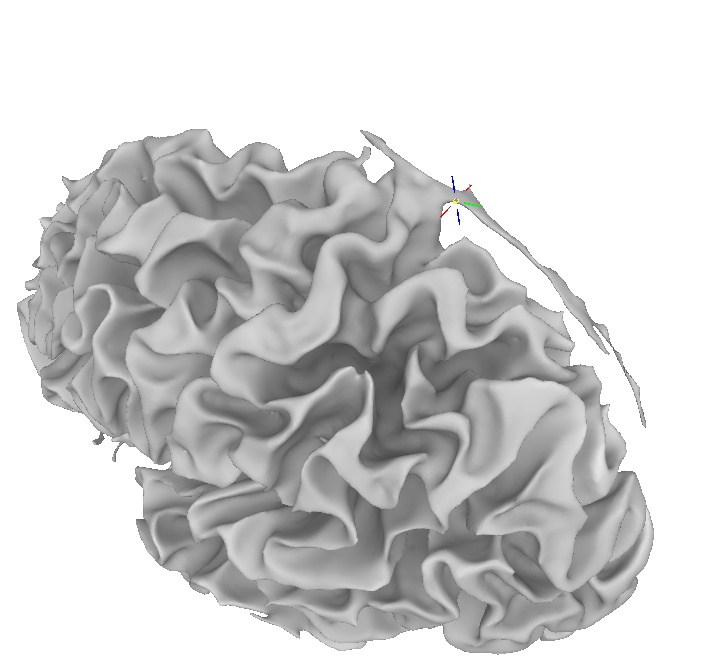

Sometimes the cortical surface model created by FreeSurfer contains large errors.

For instance, in this picture, part of the pia-arachnoid-dura has been classified as part of the cortex.

Then, rerun the surface creation routine.